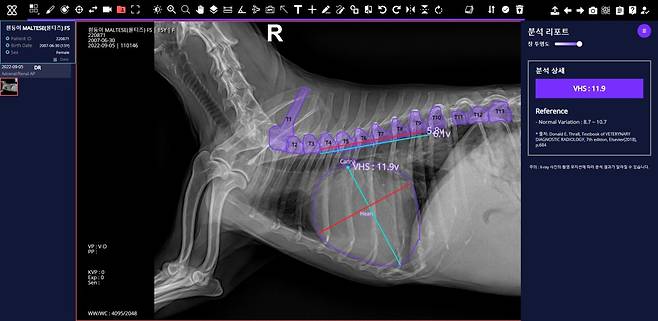

“말을 못 하는 반려동물을 위한 기술이어서 더 가치가 있다고 생각한다. 엑스레이 촬영한 것을 클라우드에 올리면 AI가 근골격계 질환, 흉부 질환 17종에 대해 10초 안에 분석을 한다. 특히 심장 크기를 측정(VHS)하는 것은 1초 만에 가능하다. 심장 크기 측정은 심장사상충 등 심장 질환 진단에 필수적인데, 그동안 수의사들은 엑스레이 사진을 보고 자로 측정할 수밖에 없었다. 정확한 위치에서 재야 하기 때문에 시간도 오래 걸렸다. 하지만 엑스칼리버는 심장의 장축(가장 긴 길이)과 단축(가장 짧은 길이)을 찰나의 순간에 정확하게 측정한다. 단축된 시간을 활용해 수의사들은 다른 강아지를 진료할 수도 있다. 아픈 동물들의 데이터를 확보하는 게 쉽지는 않았지만 엄청나게 많은 데이터를 학습시켜 분석 속도와 정확도, 진단할 수 있는 질환 종류를 확대하고 있다. 현재는 엑스칼리버가 강아지들의 질환을 판독할 수 있는데, 앞으로 고양이 등 반려동물의 종류도 확대하는 게 목표다. 현재 100여개가 넘는 병원에서 엑스칼리버를 도입했고, 많은 반려인에게도 환영받고 있는 것으로 알고 있다.”